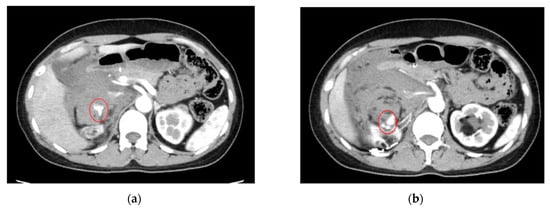

- AI for Image Analysis: AI-based image analysis algorithms can enhance the detection and diagnosis of extravasation events in imaging studies, such as ultrasound, MRI, and CT. These algorithms can automatically identify subtle signs of extravasation, assist healthcare providers in interpreting the imaging findings, and facilitate a timely intervention. This suggestion is subsequently extended as a separate discussion.